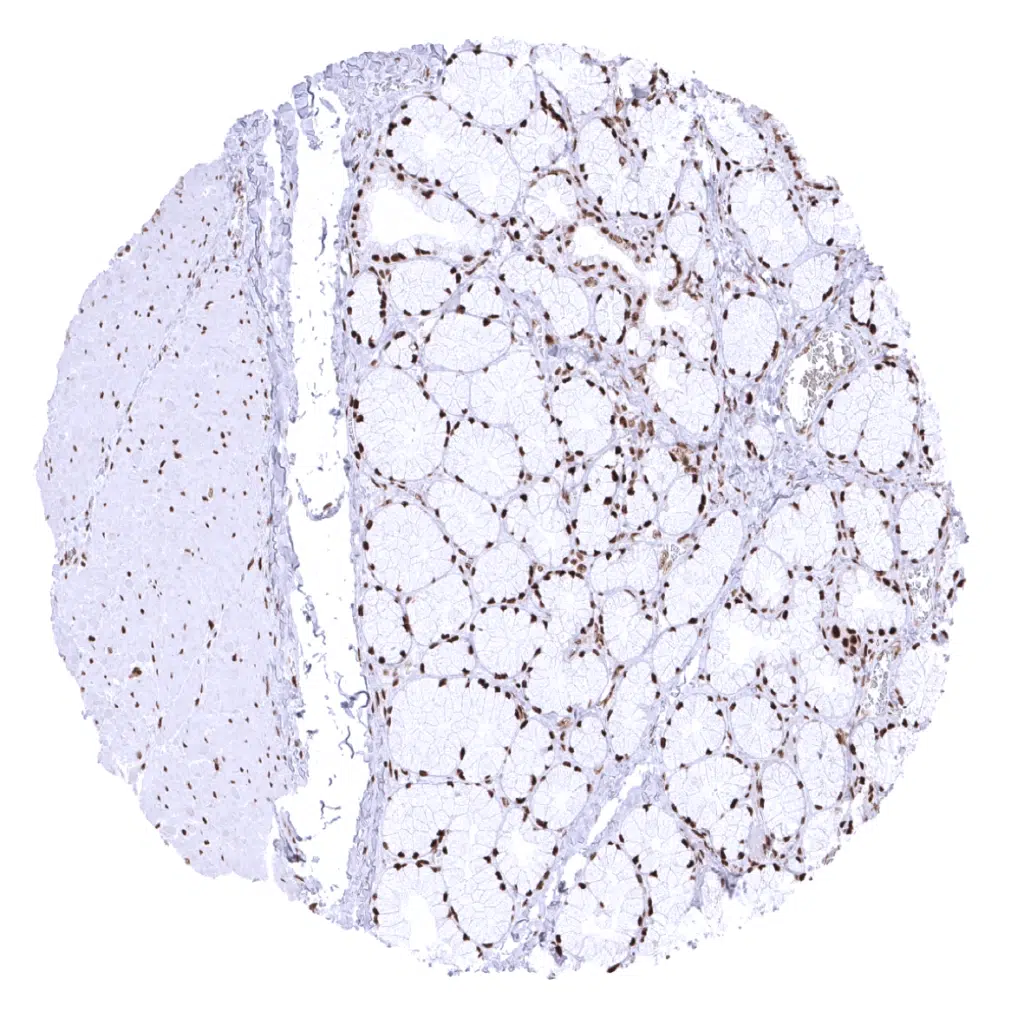

Fat